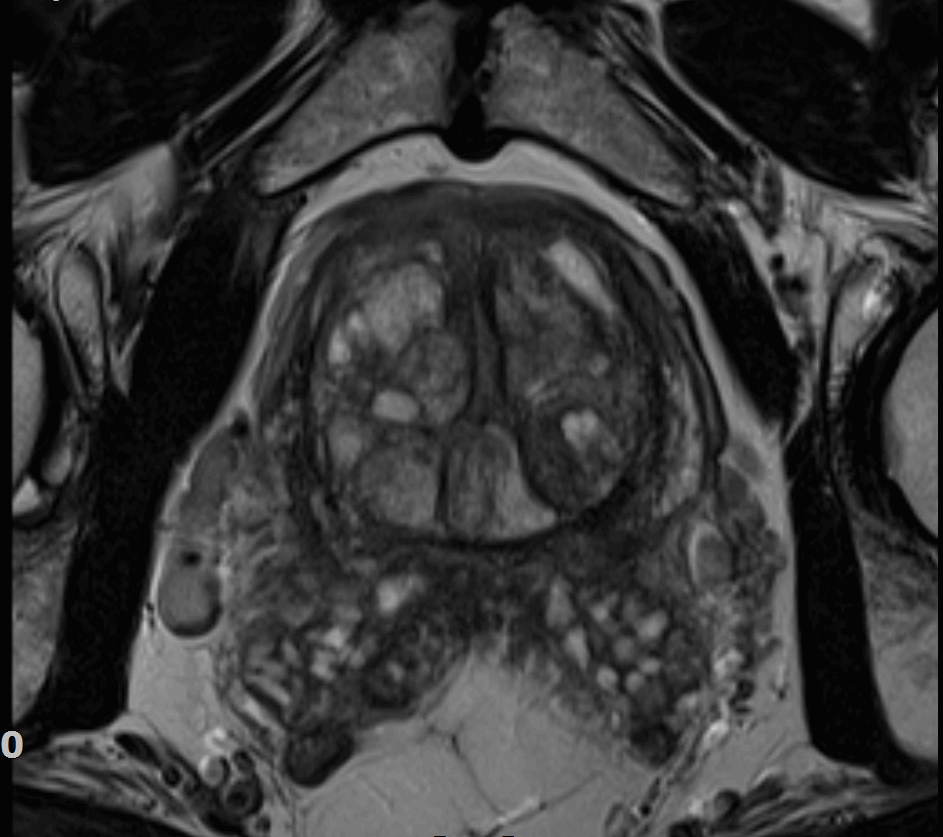

Magnetska rezonanca prostate

Trenutačno najsuvremenija dijagnostička metoda za rak prostate je magnetska rezonancija na MR uređaju jakosti 3Tesle. MR prostate na MR 3Tesle možete obaviti u Poliklinici Medikol u Zagrebu i Splitu. Pretraga je za pacijenta potpuno bezbolna i bez ioniziranog zračenja.